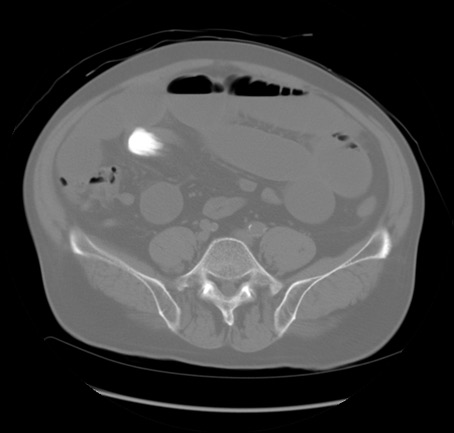

症例20(横断像)

【症例】 60歳代男性

【主訴】 腹部膨満、嘔吐

【現病歴】5日前頃より倦怠感を認め食事量減少し4日前の朝嘔吐、食事摂取困難となった。 3日前近医受診し点滴施行され整腸剤などを処方された。 当日他院を受診し、腹部膨満著明、炎症反応の上昇(CRP10.8、WBC11200)あり、紹介受診となる。

【身体所見】 意識JCS1 受け答えがはっきりしないBP 111/57mHg、 P 67bpm、、BT35.2°C、SpO2 97%(RA)、 腹部:膨隆、打診で鼓音あり、全体的に圧痛有り、腸蠕動音(-)、反跳痛ははっきりせず。

【データ】WBC 11400、CRP 14.20